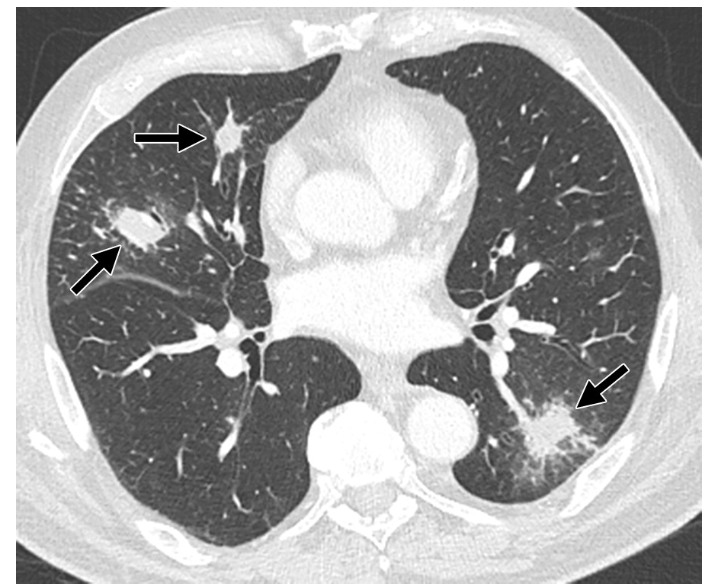

Valley fever is common name of deadly fungus Coccidioides immitis or Coccidioides posadasii.

Can affect any body organ.